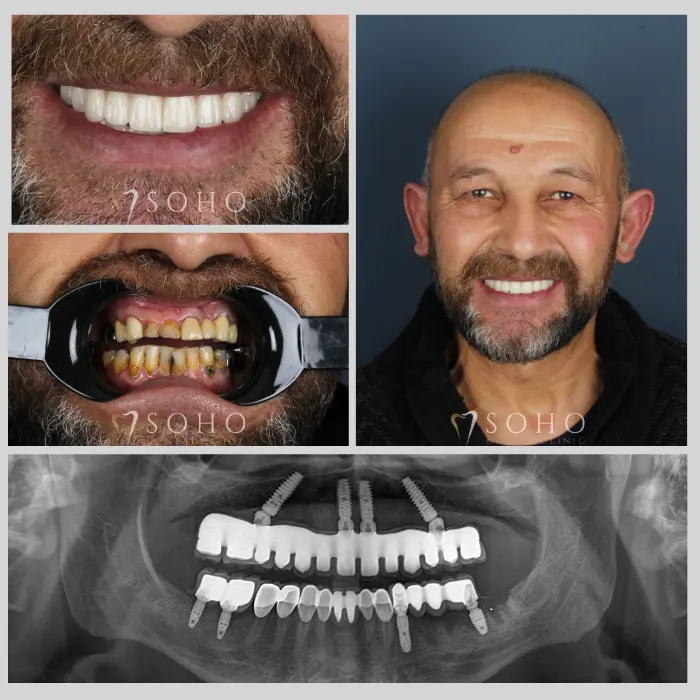

Real Patients. Real Smiles.

Explore the journey of our international patients through authentic visuals, elegant transformations, and moments captured inside Soho Dental Clinic. Let their stories inspire your own.

From First Visit to Final Smile.

Explore real patient stories captured in every transformation. These are more than smiles — they are renewed confidence, achieved with care and precision at Soho Dental Clinic.